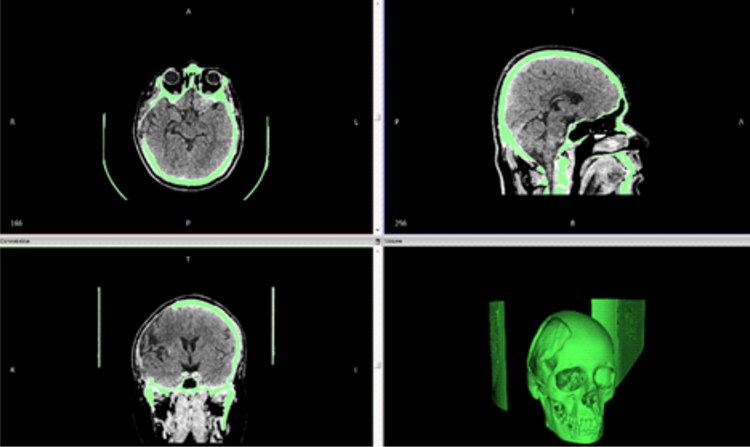

CONSTRUCTION OF A 3D-IMPLANT MODEL

On the basis of the virtual 3D-patient model an implant model is constructed. After consultation between you, the treating physician, and our technical designers, you determine the final implant shape. The consultation can take place either via telephone or via E-mail. If necessary we send you also real 3D- model for the implant planning.

Patient-specific implants are designed and produced according to patient-derived CT data for excellent reconstructive results. Our main products are patient-specific implants for the brain- and face-skull areas. These patient-specific implants can, for example, become a necessity after trauma, tumour surgeries, surgery accesses. This new procedure allows us to create implants that are custom-made for every patient.

Data acquisition

First of all, the necessary data of the patient is gathered with the imaging procedure like computer tomography and afterward stored, e.g. in DICOM- format.

The data of the patient is prepared and converted by us; a virtual 3D-patient model is created.